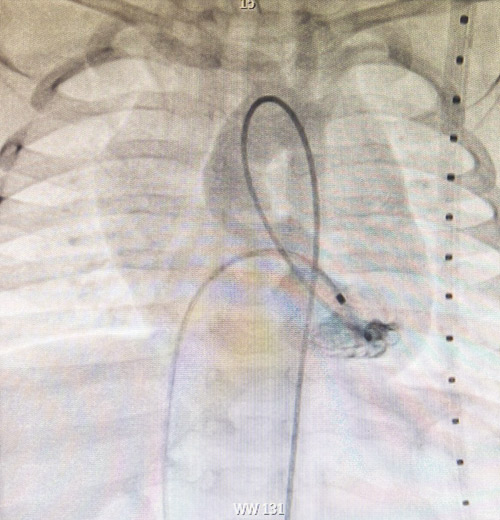

وقال تجمع القصيم الصحي إن أطباء قسم أمراض القلب أطفال مركز الأمير سلطان لطب وجراحة القلب بمنطقة القصيم تمكنوا من القيام بإجراء قسطرة قلبية عاجلة لطفل يزن تسعة كيلوجرامات أوضحت الفحصوات السريرية والمخبرية أنه يعاني من حالة انسداد شديد في صمام الشريان الأورطي الذي لم يكن ظاهراً لأهل الطفل بشكل واضح أثناء إجراء الكشف الاعتيادي عليه في عيادة المستشفى، الأمر الذي استدعى القيام بالمزيد من التحاليل والفحوصات الدقيقة بالأشعة المقطعية.

وأشار أن الفريق الطبي المشرف على الحالة قرر على الفور بعد أن تبين حالة الانسداد له في الفحوصات في صمام الشريان الأورطي إجراء تدخل طبي وعمل توسيع بالوني للصمام عن طريق القسطرة، وقد تكللت العلمية بالنجاح وتم نقل الطفل للرعاية القلبية وهو في حالة مستقرة، وغادر بعدها المركز وهو بصحة جيدة.